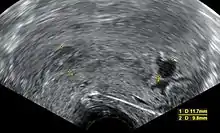

An ultrasound showing a gestational sac containing a yolk sac but no embryo

An anembryonic pregnancy (also called an "empty sac" or "blighted ovum") is a condition where the gestational sac develops normally, while the embryonic part of the pregnancy is either absent or stops growing very early. This accounts for approximately half of miscarriages. All other miscarriages are classified as embryonic miscarriages, meaning that there is an embryo present in the gestational sac. Half of embryonic miscarriages have aneuploidy (an abnormal number of chromosomes).[50]